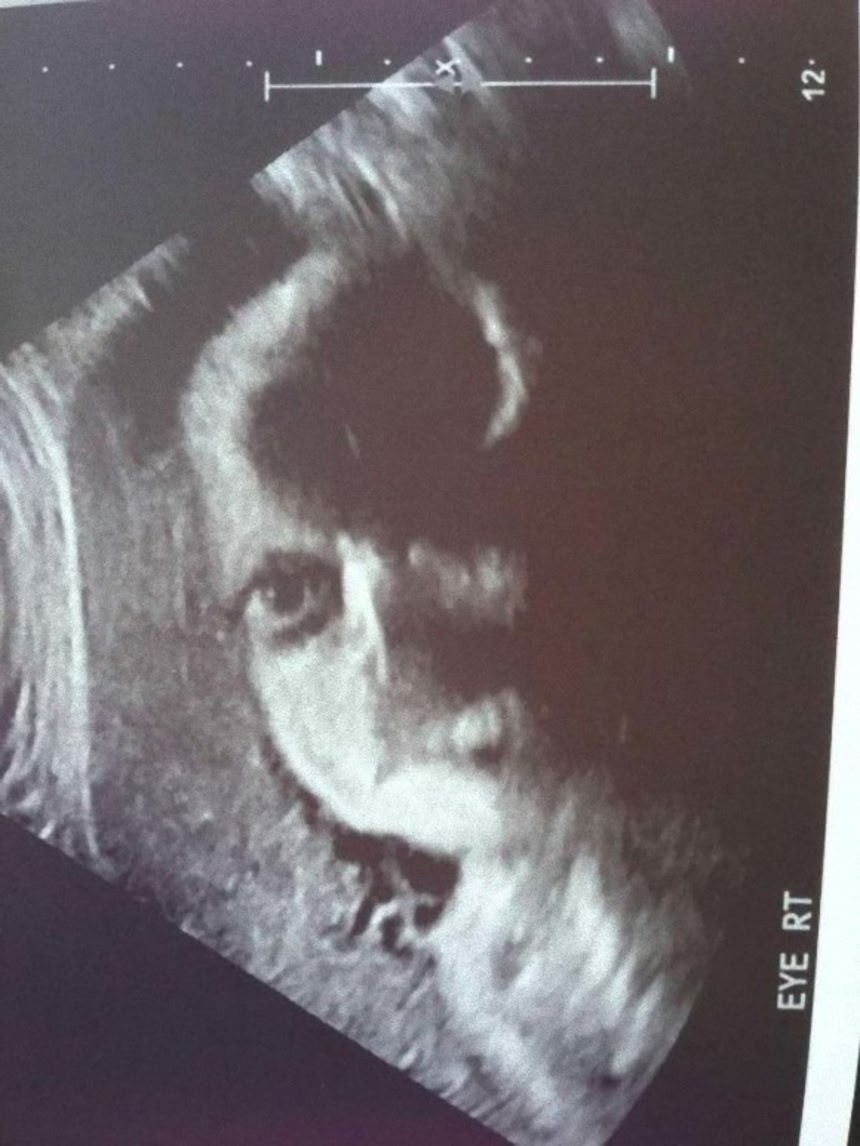

人間の脳は、3つの点が集まった図形を人の顔と見るようにプログラムされているようにできている。これはシミュラクラ現象と呼ばれるものなのだが、モノクロで撮影された胎児の超音波写真は、見方によってはホラーとしか言えない悪夢的光景が潜んでいるようなんだ。

これらの超音波写真は、親御さんがネット上で公開したもので、見方によっては腹にやばいものが宿っているように見えるものだ。

7とかはどういう具合でああなっちゃったんだ?

エコーであんな普通の写真みたいには写らないよね。

7番目の画像はコラの可能性があるな。眼だけが実写のようで怪しい。

うちの子のときは眼球なんて写らなかったよ